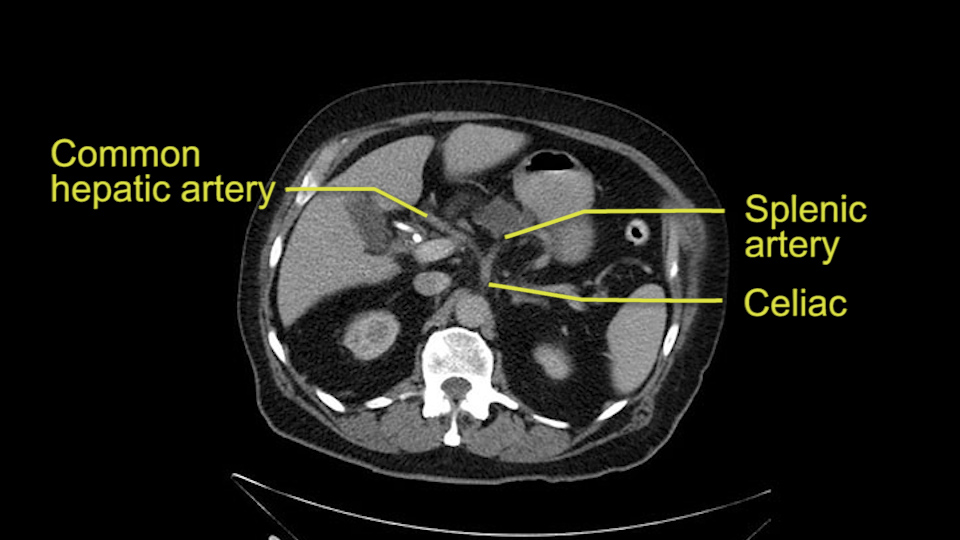

Then you look for anomalies. The one you worry about the most doing a Whipple is a replaced or aberrant right hepatic artery coming off the SMA at its origin. So again, find the SMA. You can find it because the renal vein goes through it. Follow it up, up-up-up. Nothing coming off of there that I can see here. Nothing coming off of it, nothing coming off of it and just to confirm it, look at the celiac trfurcation. There’s the celiac, there’s the bifurcation, there's the splenic artery, hepatic artery. Make sure there’s a right, which there is here. The right usually goes under the bile duct: important when you’re going around the bile duct to do a Whipple. A replaced right goes under the portal vein and the bile duct way over here on the right. That’s about it.

To plan a pancreatoduodenectomy, we start by reviewing the vascular anatomy, especially the origin of the celiac trunk, here, in front of the aorta, looking for any evidence of stenosis. In addition, we look at the origin of the superior mesenteric artery, to look for any branches, and any replaced right hepatic arteries coming from the superior mesenteric artery; which does occur in about 12% of the population.

First, the stenosis of the celiac trunk, which can be caused by arteriosclerosis, especially in a patient who is 83, or in patients who have arcuate ligament; we do see it, sometimes in much younger patients. In those cases, it may be that the circulation of the hepatic artery comes entirely from the gastroduodenal artery and its anastomoses, through the pancreaticoduodenal arteries, coming from the superior mesenteric artery. This means that before the gastroduodenal artery is ligated, we first clamp and wait 30 seconds to a minute, to feel and check the arterial inflow to the liver. If the pulse is diminished or there is a complete absence of the pulse, the surgery should be modified or probably a pancreatoduodenectomy cannot be done, because of the risk - when ligating the gastroduodenal artery - of causing fulminant hepatic ischemia postoperatively.

The second point about the vascular anatomy-, is to again look for right hepatic arteries in the hilum, coming from the superior mesenteric artery by palpating-through the Winslow Hiatus. Usually we will check for a pulse in the posterior aspect of the hepatic hilum, where a right hepatic artery should not usually be found. In this case, the precaution is to avoid an accidental ligation of the right hepatic artery that might jeopardize perfusion of the right lobe, or if there is a completely replaced hepatic artery that can put the liver circulation at risk.